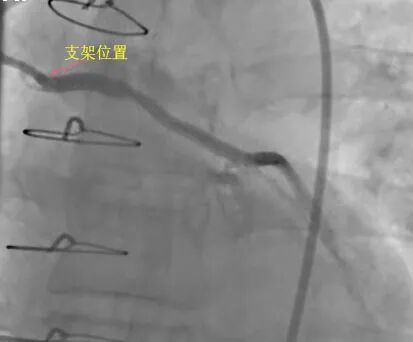

OCT显示该患者SVG近段病变处有血栓及脂质斑块(图2),经过团队充分讨论后,考虑直接植入支架极易出现无复流或慢血流,需要先于SVG预置远端保护装置,并根据OCT测算病变血管直径和长度,选择合适尺寸的支架。最终在SVG病变处成功植入4.5×18mm支架一枚并充分后扩张,造影显示手术即刻效果非常理想(图3),进一步行OCT显示支架贴壁良好、边缘未见血管夹层、无膨胀不良(图4)。术中病变血管也未出现无复流或慢血流。

图3术后造影结果

图4术后OCT显示支架贴壁良好